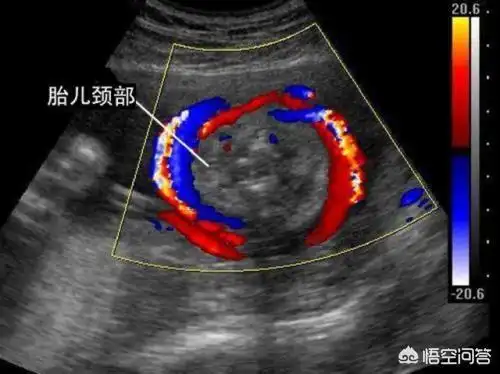

看胎儿的b超图像,胎儿的颈部会有u型压迹,超声提示会备注胎儿脐带绕颈